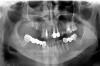

rital Опубликовано 2 июня, 2009 Автор Поделиться Опубликовано 2 июня, 2009 1. а, получается только за синус сотка. Это дороговато Кстати я не знаю чем один синус от другого отличается, чтобы там уровни сложности выставлять.2. Ритал - я согласен с Анндой, мы вам сказали что делать, а вы только пишите на форуме одно и тоже. Найдите себе ЛОРа сами. Вчерашний день прошел у вас зря. Судя по всему - стало хуже.Тема будет продолжена, когда дойдете до ЛОРа.1. Когда посмотрите на снимок, то поймете, что он СЛИШКОМ завысил цену, ну да что теперь делать... Почему там только 2 "шурупа" (не знаю как правильно называется), я думала сколько имплантов будет ставиться, столько и отверстий д.б. в верх челюстной кости... Если не трудно объясните2. Согласна, действительно получается, что я одно и тоже вам пишу и пишу, но вот мои действия: 1) сделала снимок (в своей поликлинике сразу в растровом формате, но родной его размер ~ 14Mb, поэтому уменьшила до половины и перевела в jpg; если окажется, что плохо что-то видно, то может по почте переслать...? Как скажете) 2) сегодня вечером никакого ЛОР врача уже не было - записали на завтра (но мне уже по-легче стало после того как вышло это обилие...) Ссылка на комментарий

Большой Зеленый Опубликовано 2 июня, 2009 Поделиться Опубликовано 2 июня, 2009 Внизу штамповку надо убирать ,37 зуб перелечивать...а может даже удалять. 33 тожеИнтересные саморезы... Ссылка на комментарий

Sahan Опубликовано 2 июня, 2009 Поделиться Опубликовано 2 июня, 2009 (изменено) 1. Когда посмотрите на снимок, то поймете, что он СЛИШКОМ завысил цену, ну да что теперь делать... Почему там только 2 "шурупа" [/quote/]Эти шурупы не имплантаты ,а для создания тента чтобы сохранить уровень нарощенной кости.К ЛОРу завтра идите все равно , как полегчало так опять хуже может стать! Изменено 2 июня, 2009 пользователем Sahan Ссылка на комментарий

Bier Опубликовано 2 июня, 2009 Поделиться Опубликовано 2 июня, 2009 шурупы - не имплантаты. Странный способ для синуса. Он в синусе блоки что-ли фиксировал шурупами+ костные чипсы. Блоками похоже он создавал новое дно пазухи. Такой способ описан в литературе. Не знаю есть ли в этом смысл. Я обхожусь костными чипсами. Ссылка на комментарий

Dr. Surkin Опубликовано 2 июня, 2009 Поделиться Опубликовано 2 июня, 2009 шурупы - не имплантаты. Странный способ для синуса. Он в синусе блоки что-ли фиксировал шурупами+ костные чипсы. Блоками похоже он создавал новое дно пазухи. Такой способ описан в литературе. Не знаю есть ли в этом смысл. Я обхожусь костными чипсами. Да. похоже, что на дно уложили блоки и укрепили их винтами. Есть такая методика - ничего особенного. Только я так думаю, что слизистая синуса давно расползлась и дополнительный костный материал в виде крошки уже вышел - смотрите по верхней и правой стенке размазню. + присоединился гайморит. Выход один - лечить как обыкновенный гайморит, а потом смотреть через 6 месяцев на КТ что осталось для имплантации. Ссылка на комментарий

Bier Опубликовано 2 июня, 2009 Поделиться Опубликовано 2 июня, 2009 Да. похоже, что на дно уложили блоки и укрепили их винтами. Есть такая методика - ничего особенного. Только я так думаю, что слизистая синуса давно расползлась и дополнительный костный материал в виде крошки уже вышел - смотрите по верхней и правой стенке размазню. + присоединился гайморит. Выход один - лечить как обыкновенный гайморит, а потом смотреть через 6 месяцев на КТ что осталось для имплантации.нет, блоки не на дно. Между блоками и дном большой промежуток. Блоками создано новое дно и они являются в данный момент крышей аугментата. Ссылка на комментарий

Dr. Surkin Опубликовано 2 июня, 2009 Поделиться Опубликовано 2 июня, 2009 нет, блоки не на дно. Между блоками и дном большой промежуток. Блоками создано новое дно и они являются в данный момент крышей аугментата. Посмотрел снимок подробнее - да - возможно и так.Однако с учетом вогнутой формы дна пазухи блок может просто лежать краями на боковых стенках - за счет этого и большой просвет. Короче - сейчас это уже не так важно. Ссылка на комментарий

Sahan Опубликовано 2 июня, 2009 Поделиться Опубликовано 2 июня, 2009 (изменено) нет, блоки не на дно. Между блоками и дном большой промежуток. Блоками создано новое дно и они являются в данный момент крышей аугментата.Читал , что такая методика используется при большой перфорации слизистой, когда невозможно ее закрыть. Мне кажется, что винты просто упираются в блоки, а не ввинчены в них. Изменено 2 июня, 2009 пользователем Sahan Ссылка на комментарий